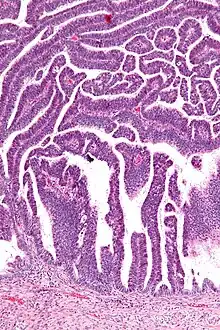

The name of the lesion describes it microscopic appearance. It has nipple-like structures with fibrovascular cores (papillae) that are long in relation to their width (villus-like), which are covered with a glandular pseudostratified columnar epithelium.

Micrograph of a villoglandular adenocarcinoma the cervix. H&E stain.

Very low magnification